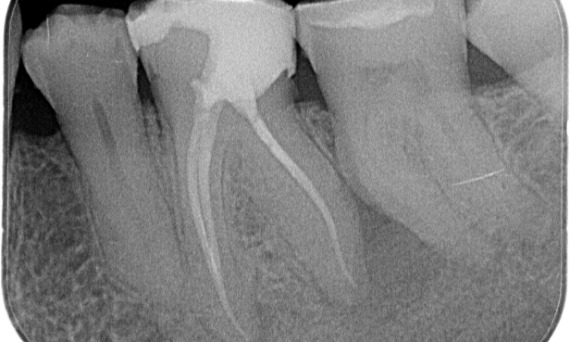

Before: Upon examination, there was a caries lesion related to the lower right first molar. Radiographic examination revealed proximity of the lesion to the pulp horn and combining it with the chief complaint, a final diagnosis of chronic irreversible pulpitis was concluded.

After: Access cavity was done as conservative as possible. TruNatomy was the system of choice due to the young patient’s age. We needed to preserve dentine as much as possible to increase the tooth ability to overcome occlusal load and increase the longevity of the final restoration.

Cairo, Egypt